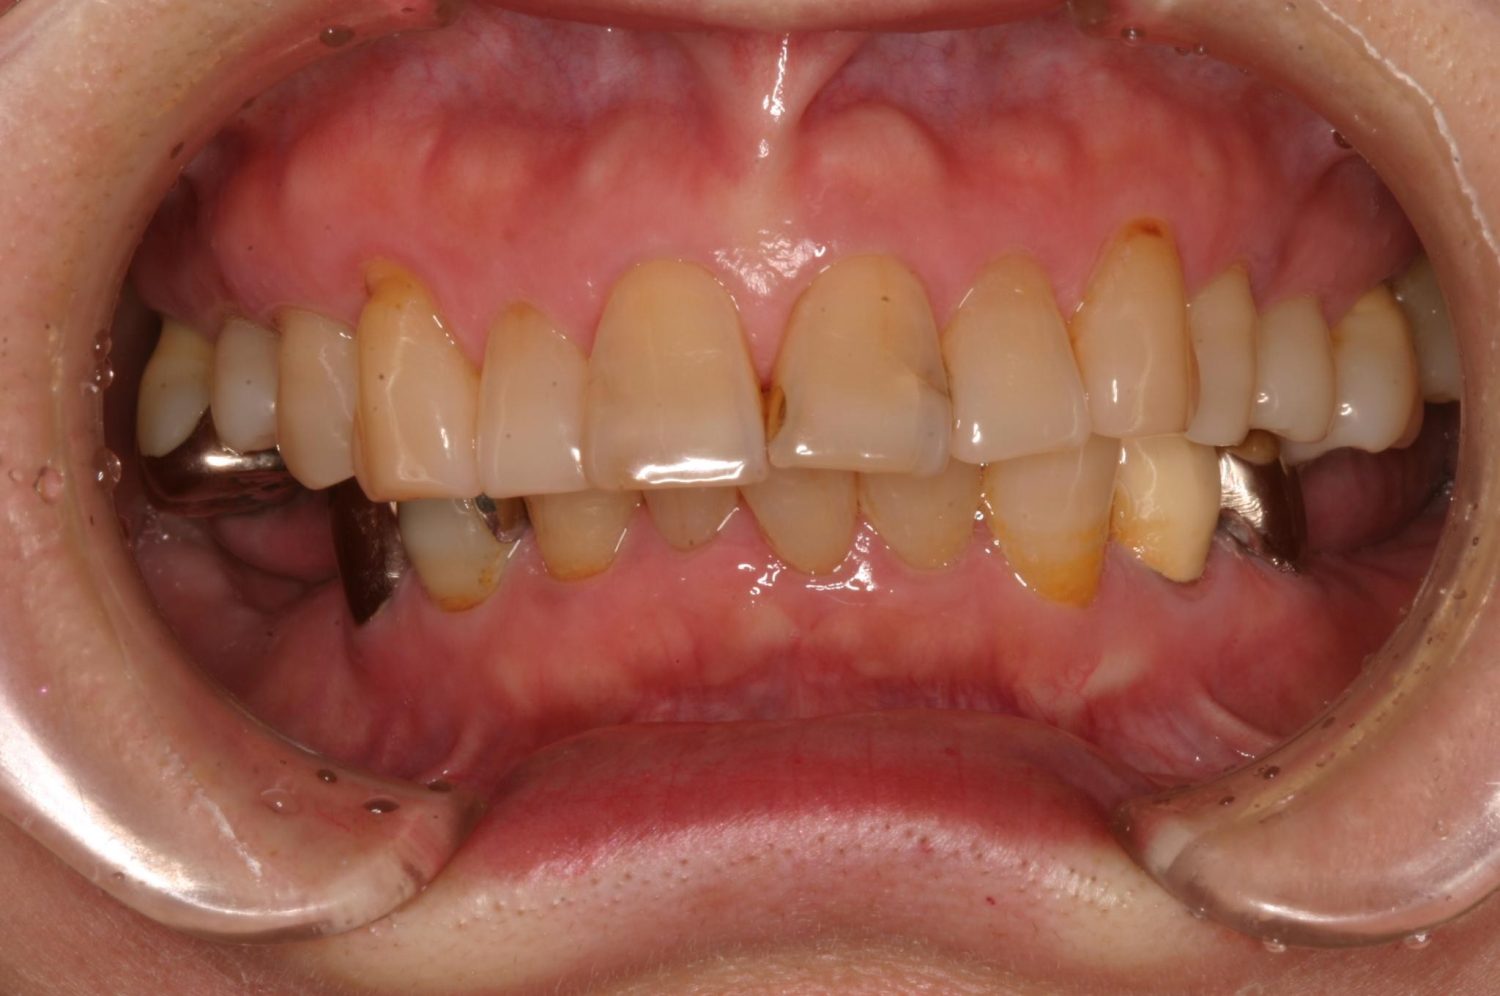

インプラント治療の症例紹介③

Before

After

主訴

むし歯の治療

治療内容

保存不可能な歯の抜歯

下顎にインプラント埋入し咬合再構成

治療費

2,688,400円(税込)

治療期間

14か月

治療回数

21回

想定されたリスク

※上部構造の形態が複雑になるため清掃が難しくなる。インプラント周囲炎の恐れがありました。

多数歯う蝕および多数歯欠損による咬合崩壊、保存不可能な歯の抜歯により上下無歯顎に。下顎に6本インプラント埋入する事で咬合再構成を行った。